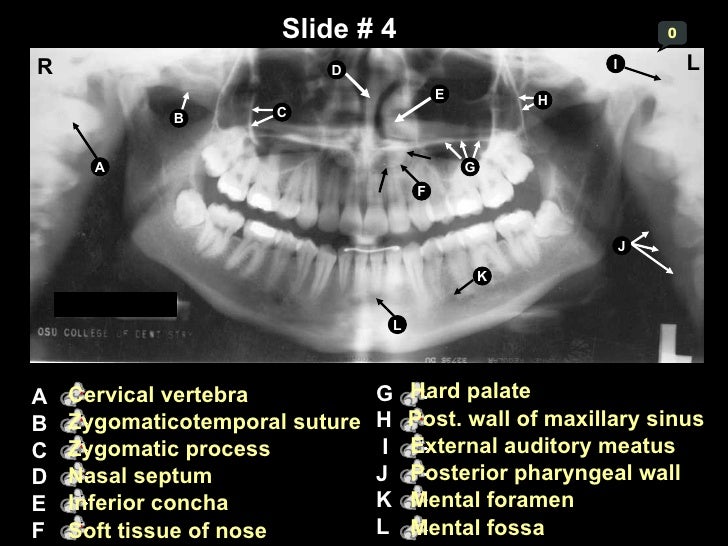

Self Study-pan-anatomy

zygomatic suture fossa zygomaticotemporal vertebra

oblique zygomatic maxillary mandible sinus suture anatomical vertebra

mandible